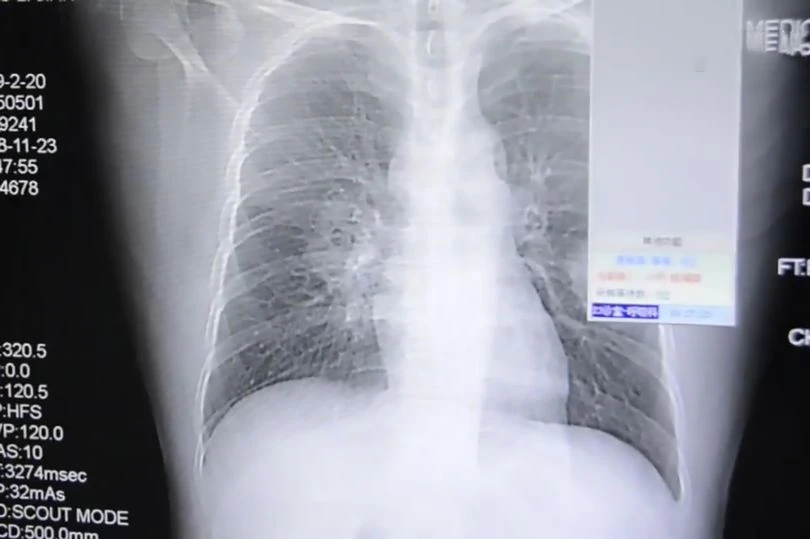

Phim chụp X-quang phổi của người đàn ông. Ảnh: ASIAWIRE

Sau một triệu chứng khó thở, người đàn ông được đưa vào cấp cứu ở bệnh viện. Sau khi chụp X-quang, các bác sĩ xác nhận ông ta đã bị nhiễm trùng phổi nghiêm trọng. Hiện ông ta đang được giữ lại bệnh viện để điều trị.